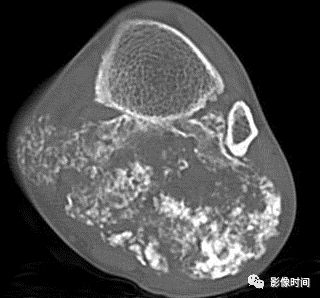

五、骨和软组织钙化

(一)瘤软骨钙化:瘤软骨常表现为环状钙化, 是诊断软骨类肿瘤较为可靠的影像学征象。环状钙化形成于环状软骨、以及软骨小叶边缘的软骨基质。钙质沉着可呈小点状、小条状、半环状或弧形;亦可浓密相连、重叠呈菜花状。钙化环的形态和密度可反映瘤组织分化程度, 通过观察钙化环的形态和密度,有助于良恶肿瘤的鉴别。

良性瘤软骨之瘤细胞分化好、生长缓慢、血供充分, 钙化环完整,密度高, 边缘清楚。良性软骨类肿瘤如骨软骨瘤(图 35)、软骨母细胞瘤(图 36)、内生软骨瘤(图 37)等均可于瘤组织内发生环形钙化。

恶性瘤软骨则呈密度淡薄, 边缘模糊的不规则钙化,恶性骨肿瘤的环形钙化,最多见于软骨肉瘤(图 38),其次是骨肉瘤。CT 是发现肿瘤内软骨钙化最为敏感的检查方法。

图 35  瘤软骨钙化:骨软骨瘤

图 36  瘤软骨钙化:软骨母细胞瘤

图 37  瘤软骨钙化:内生软骨瘤

图 38  瘤软骨钙化:软骨肉瘤